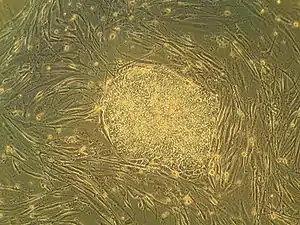

Algunas de las aproximaciones biomédicas dentro del campo de la medicina regenerativa, pueden implicar el uso de células raíz, también denominadas células madre.[8] Los ejemplos incluyen la inyección de células de raíz o células progenitoras obtenidas a través de diferenciación dirigida (terapias celulares); la inducción de regeneración por moléculas activas biológicamente, administradas solas o como secreción por células infundidas (terapia de inmunomodulación); y trasplante de tejidos y órganos crecidos en vitro (ingeniería de tejidos).[9][10]